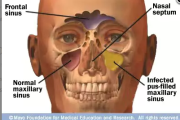

Ülalõuaurkepõletik

Sinuiiti diagnoositakse ülemiste hingamisteede sümptomitega täiskasvanuil ja üle4-aastastel lastel ultraheli abil. – Antibiootikumi määratakse ainult neile patsientidele, kellel on leitud ülalõuaurkes eritist. – Sinuiit on astmahaige seisundi halvenemise põhjus. – Korduvate … Loe edasi »